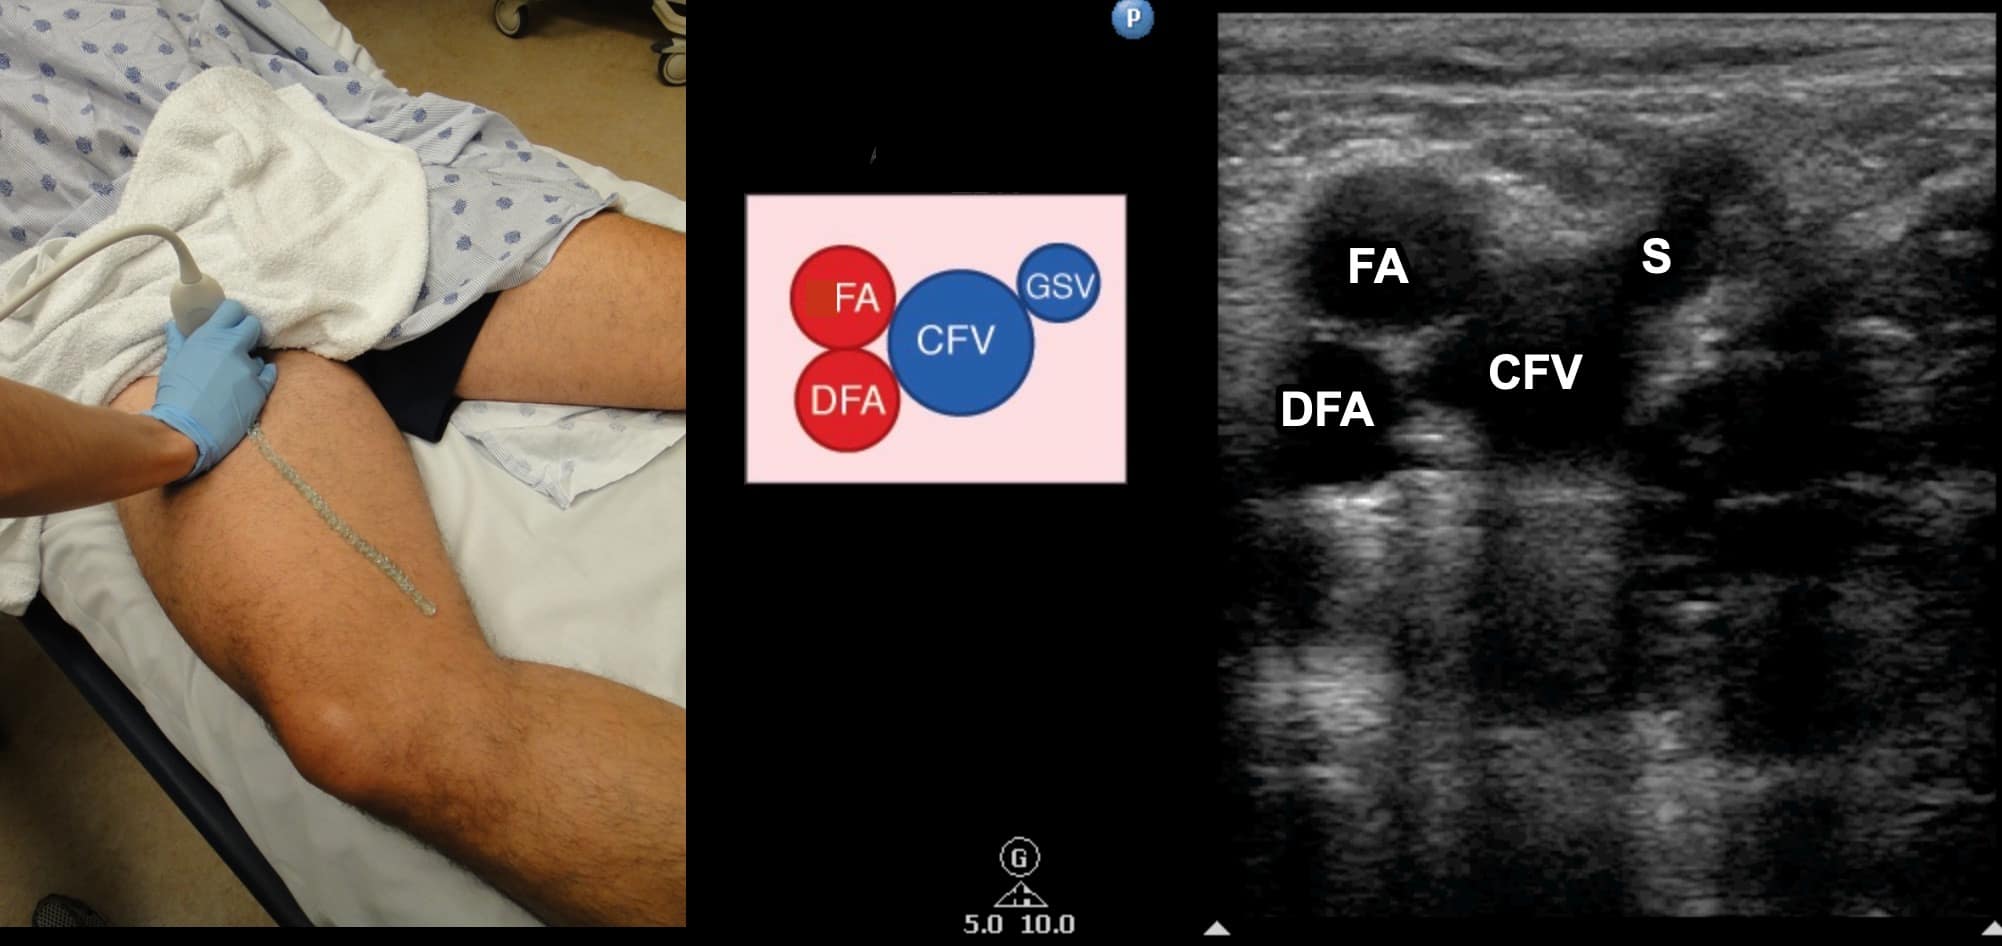

Due to its location in the pelvis, the EIV can be difficult to visualize, so the proximal protocol begins with the transducer in the transverse position high in the groin, just distal to the inguinal ligament with the CFV at the saphenous vein (SV) branch point visualized (Figure 3). A normal vein will be anechoic and easily compressible (Figure 4). Compression should be performed with the transducer transverse to the vein with compression being directed in an anterior-posterior direction. Compression should not be performed in a longitudinal plane to the vein since false-positive results can occur from “side-walling” and sliding off the vein, which can appear sonographically as a true compression. Tenting of the artery means that more than enough pressure has been applied.

Figure 3. Split screen demonstrating transverse window of common femoral vein (CFV)/greater saphenous vein (S) junction with transducer position (indicator toward patient’s right).

The transducer is directed in a caudal direction following the CFV with intermittent compressions performed at 1-2 cm intervals looking for lack of compressibility or evidence of intraluminal echogenicity. The common femoral artery (CFA) will be noted first to divide into the femoral artery (FA) and profunda femoral artery (PFA) (Figure 5). The CFV is followed until it divides into the FV and the PFV with intermittent compressions continued (Figure 6). The PFV is an unlikely location of isolated LE DVT and does not need to be followed.

Figure 5. Split screen demonstrating transverse window of femoral artery (FA) and deep femoral artery (DFA) along with common femoral artery (CFV) and saphenous (S) vein with transducer position shown.